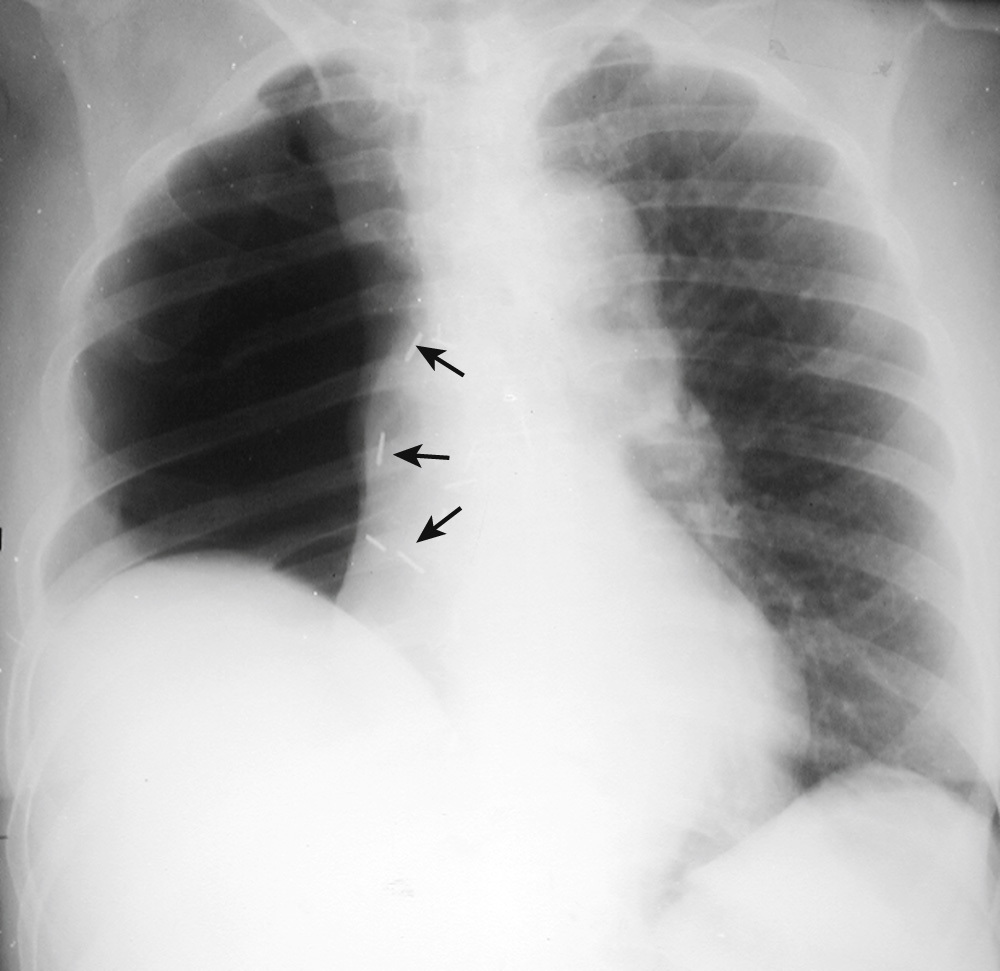

What is going on in this CXR?

Subsegmental atelectasis

Subsegmental atelectasis produces linear densities of varying thickness usually parallel to the diaphragm, most commonly at the lung bases. It is most likely related to deactivation of surfactant

It occurs mostly in patients who are “splinting” (i.e., not taking a deep breath), such as postoperative patients or patients with pleuritic chest pain

It can look almost identical to linear lung scarring, however subsegmental atelectasis will change/disappear over days.